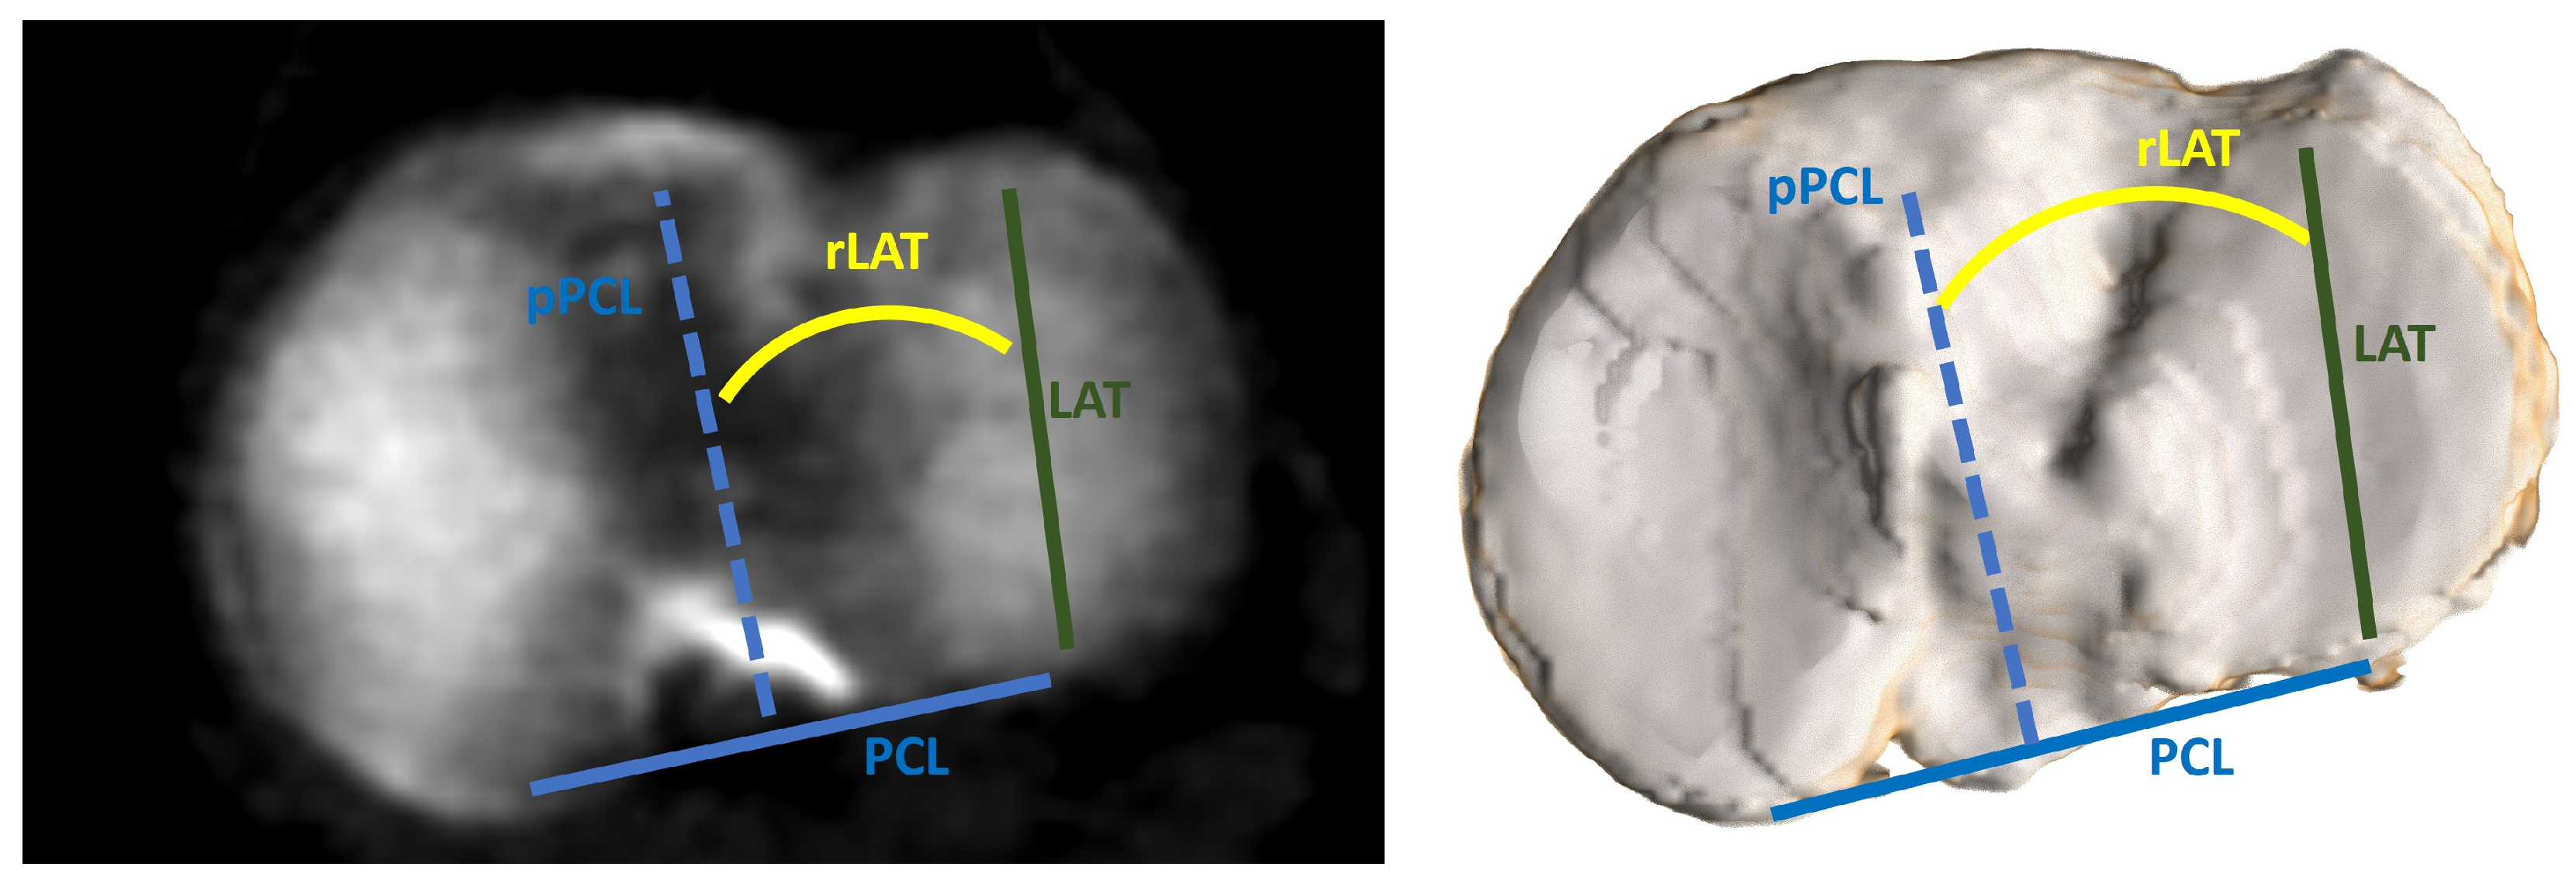

| rLAT, ° | −6.5 ± 3.3 (−13.0–3.8) |